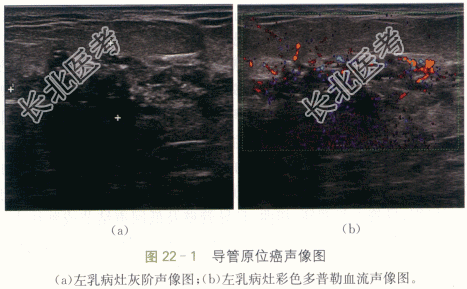

左乳导管原位癌。